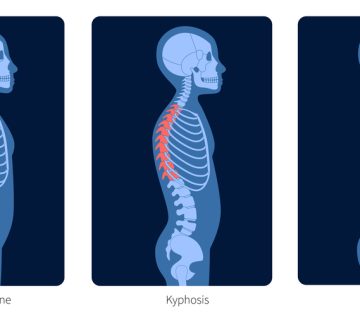

اسکولیوز دژنراتیو (Degenerative Scoliosis) که گاهی به آن «اسکولیوز بزرگسالان» یا «اسکولیوز دِ نوو (de novo)» هم گفته میشود، نوعی انحراف جانبی ستون فقرات است که در دوران بزرگسالی ظاهر میشود یا در اثر تغییرات ناشی از افزایش سن، بدتر میشود. پزشکان معمولاً آن را به عنوان وقتی زاویهی انحراف ستون فقرات (زاویهی کاب) در عکس رادیولوژی بیش از ۱۰ تا ۲۰ درجه باشد، تعریف میکنند.

این نوع اسکولیوز با اسکولیوز ایدیوپاتیک نوجوانان (AIS) فرق دارد. در اسکولیوز نوجوانان، علت بروز معمولاً اختلالات رشد ستون فقرات در دوران بلوغ است. اما در اسکولیوز دژنراتیو، عامل اصلی، «فرسودگی و تخریب بافتها» بهمرور زمان است. دیسکها بین مهرهها به تدریج آب خود را از دست میدهند، ارتفاعشان کم میشود، گاهی یک طرف بیشتر از طرف دیگر فشرده میشوند و این مسئله باعث انحراف ستون فقرات میگردد. همزمان، مفاصل کوچک پشت ستون فقرات (فاستها) دچار آرتروز میشوند و استخوانها به دلیل پوکی استخوان ضعیف میگردند. همهی این تغییرات میتواند باعث خم شدن یا انحراف ستون فقرات شود.

این نوع اسکولیوز بیشتر در ناحیهی کمری (lumbar) دیده میشود، اما میتواند بخش میانی ستون فقرات (thoracic) را هم درگیر کند. در بسیاری از بیماران، این انحراف همراه با خمیدگی به جلو (عدم تعادل ساجیتال) دیده میشود که مشکلات بیشتری مثل خستگی زودرس و کاهش توانایی حرکت ایجاد میکند.